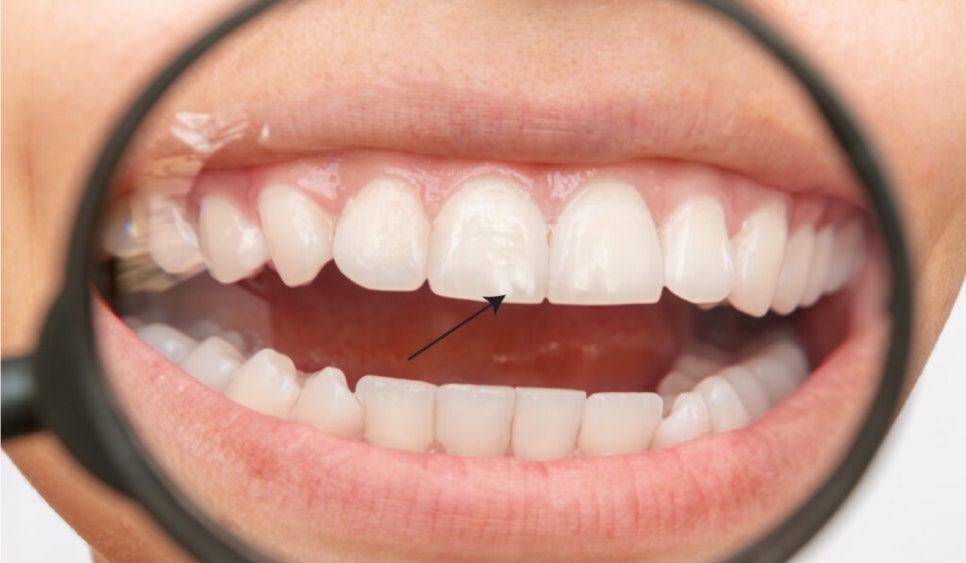

앞니 백색반점: 치아탈회의 결과

치아의 백색반점은 '치아탈회' 증상 중 하나입니다.

치아탈회는 미네랄을 잃어 생기는데

이는 유전적인 이유일 수도 있고

불소과다, 혹은 산에 의해

법랑질 표면의 미네랄이 소실되어

하얀얼룩이 생길 수 있습니다.

일상생활에서 반점치가 생기는

대표적인 경우는 다음과 같습니다.

☑️치아 형성기에 불소과다에 노출되어

법랑질 결함으로 치아변색

☑️교정기 착용 후 관리 부족

☑️입 안 산성환경 (산성음식/세균/역류성식도염)

☑️양치질 등 위생관리 소홀

☑️외부충격으로 인한 법랑질 손상